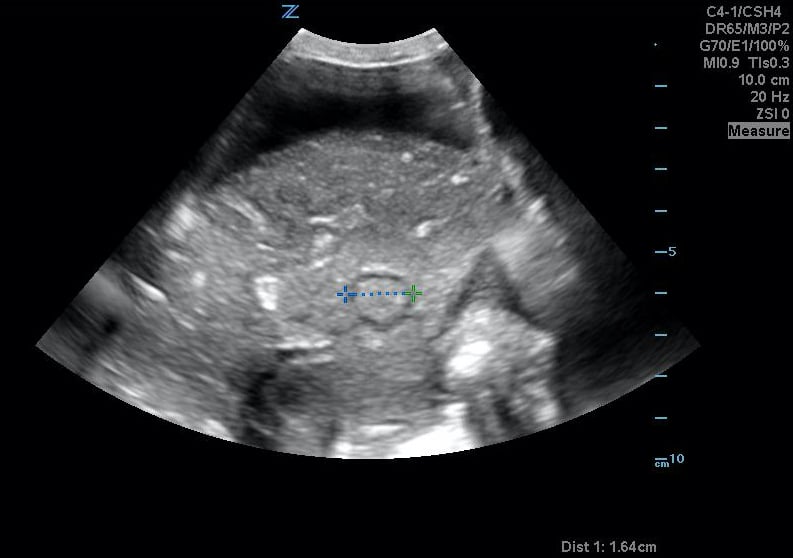

Figure 29. Transverse suprapubic view revealing the fetal cranium in the pelvis, consistent with a vertex presentation. Note the calipers measuring a bi-parietal diameter at 30 weeks and 6 days.

- Mechanical Risk Factors for Delivery